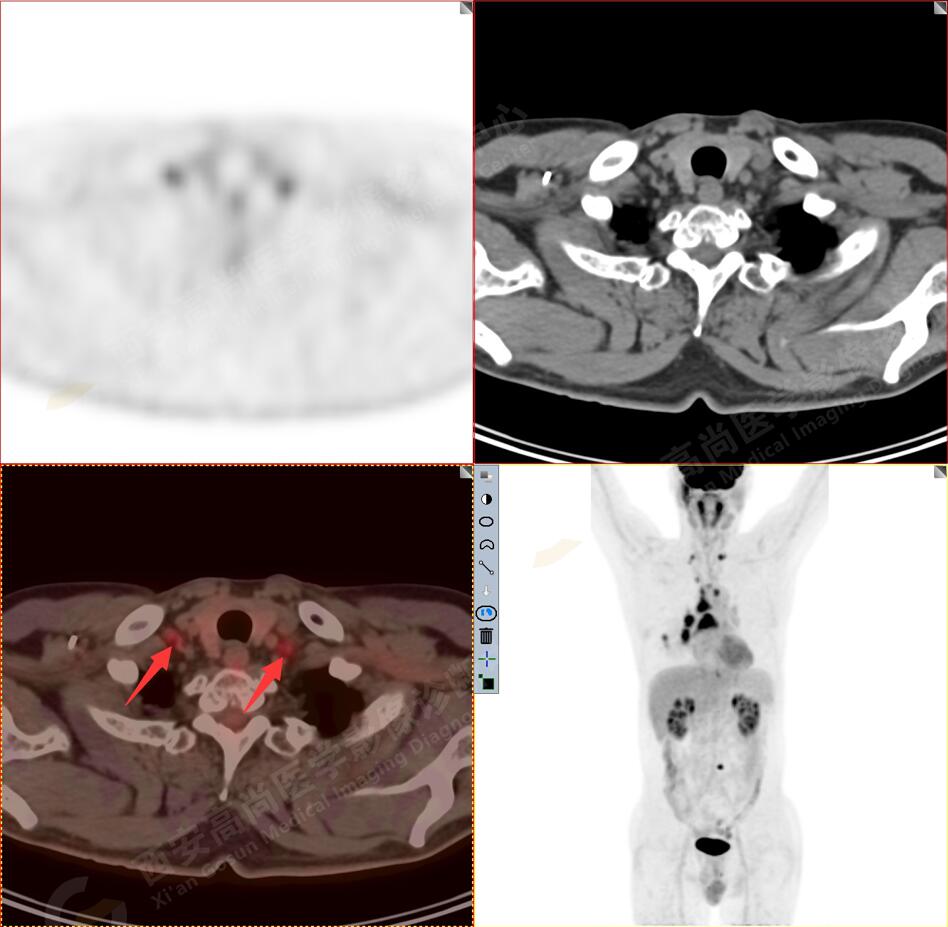

2.以下為全身多發(fā)轉移灶

3.右側肺門、縱隔(1L、1R、3A、4、6、7組)及雙側鎖骨上多發(fā)腫大淋巴結,呈不同程度FDG代謝異常增高,考慮為淋巴結轉移。